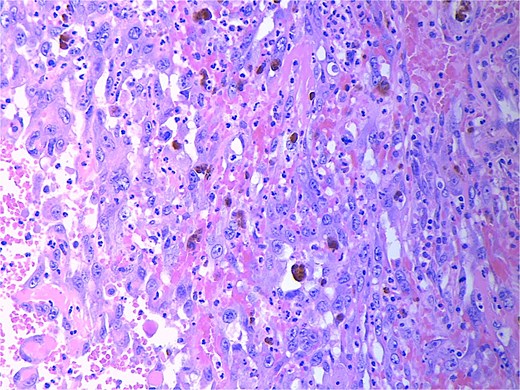

High power magnification (20×) H&E showing malignant cells forming vascular channels with atypia and multiple mitotic figures.

High power magnification (40×) H&E showing malignant cells forming vascular channels with atypia.